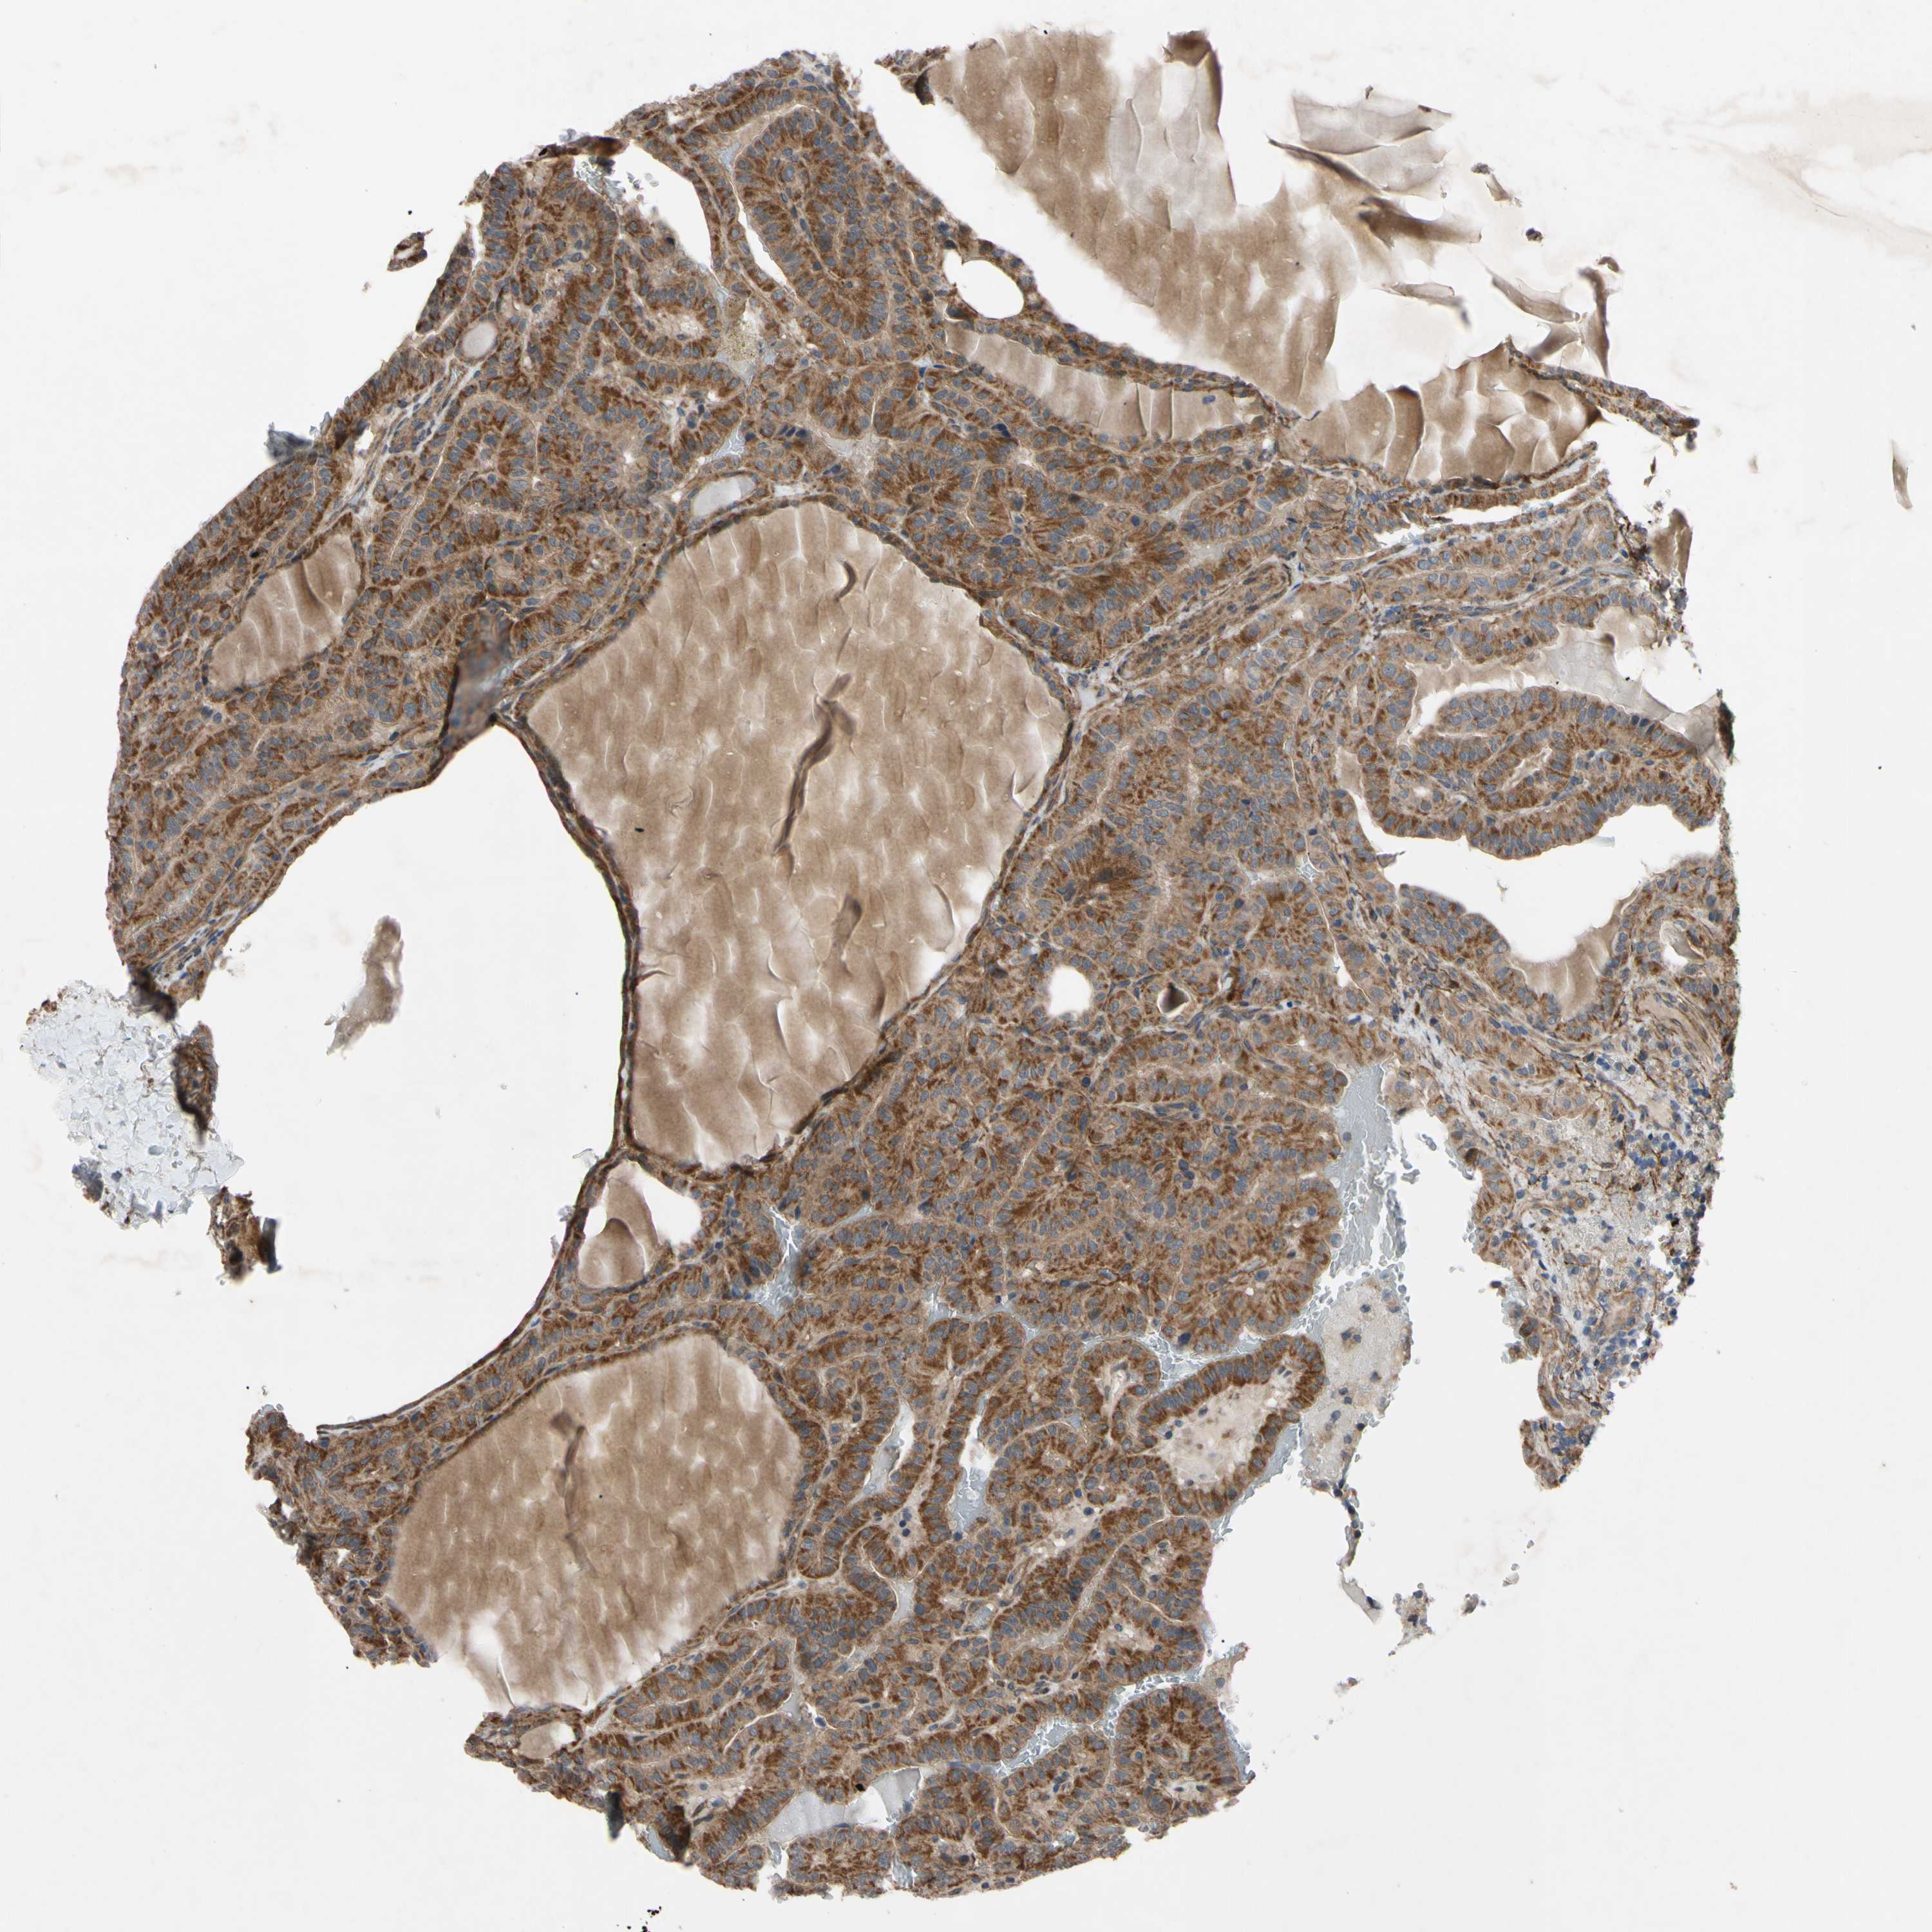

THYROID CANCER - Protein expressioni

A mouse-over function shows sample information and annotation data. Click on an image to view it in a full screen mode. Samples can be filtered based on level of antibody staining by selecting one or several of the following categories: high, medium, low and not detected. The assay and annotation is described here.

Note that samples used for immunohistochemistry by the Human Protein Atlas do not correspond to samples in the TCGA dataset.

Antibody stainingi

Antibody staining in the annotated cell types in the current human tissue is reported as not detected, low, medium, or high, based on conventional immunohistochemistry profiling in selected tissues. This score is based on the combination of the staining intensity and fraction of stained cells.

Each image is clickable and will lead to virtual microscopy that enables deeper exploration of all samples and also displays staining intensity scores, fraction scores and subcellular localization as well as patient and tissue information for each sample.

Antibody HPA020095

Antibody HPA020138

Antibody CAB010878

Antibody CAB080402

Staining

High

Medium

Low

Not detected

Intensity

Strong

Moderate

Weak

Negative

Quantity

>75%

75%-25%

<25%

None

Location

Nuclear

Cytoplasmic/membranous

Cytoplasmic/membranous,nuclear

Papillary adenocarcinoma, NOS

Follicular adenoma carcinoma, NOS